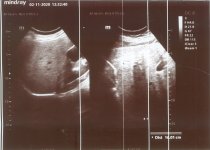

- استشاري موجات صوتية Fatty liver although normal size + Bilateral AKI more evidence in Rtside